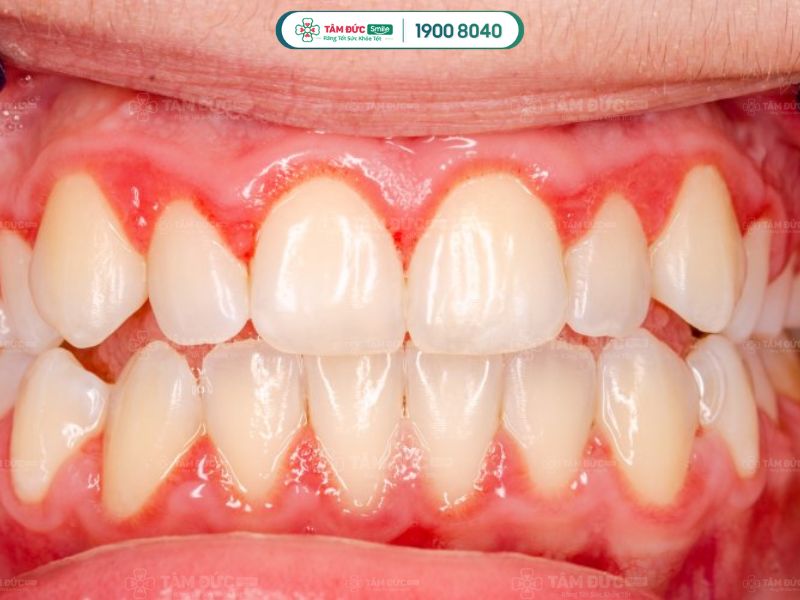

2.2. Viêm lợi

Không đánh răng trước khi đi ngủ lâu ngày tạo điều kiện cho mảng bám tích tụ quanh chân răng. Từ đó, vi khuẩn gây tổn thương lợi, làm chảy máu và sưng đau. Nếu không được chăm sóc và điều trị kịp thời có thể dẫn tới nguy cơ tụt lợi, răng lung lay.

Không đánh răng đều đặn dẫn đến viêm lợi